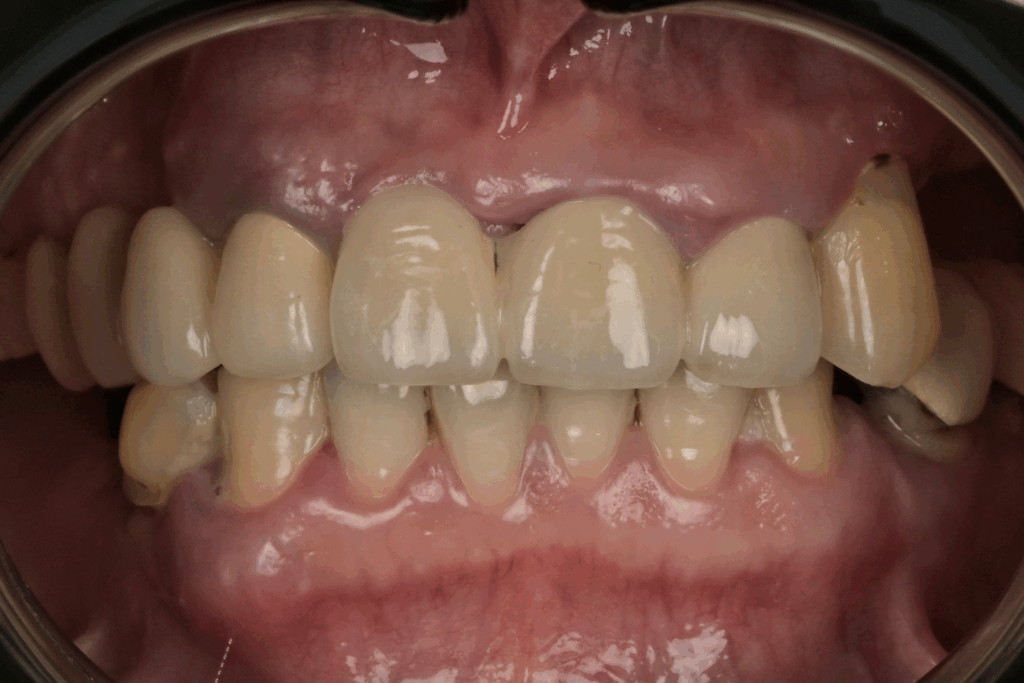

案例1. 上顎+下顎All on X

Before

After